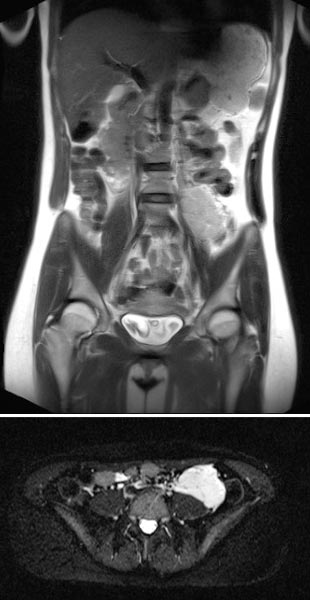

Koronare native T2-Haste-Sequenzen zur Verlaufsbeurteilung der VM ventral auf dem linken Musculus psoas aufsitzend in der 21. Schwangerschaftswoche. Während der Gravidität entwickelt die Patientin auch eine Harnstauungsniere Grad III rechts.

In der axialen T2-HASTE-Sequenz in der 21. Schwangerschaftswoche grenzt die VM an die Plazenta, ohne Verdrängung oder Verlagerung von Uterus oder des Fötus.